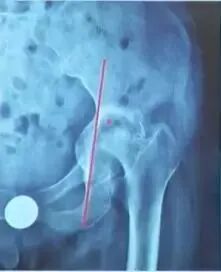

开口位置可以决定股骨颈前倾角方向:

前倾角:股骨颈轴线与股骨后髁连线的夹角,可在一定范围调节

——开口偏前,减小前倾角;

——开口偏后,增加前倾角。